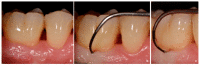

Various classification systems have been proposed to describe furcation lesions and Glickman's classification for many years seems to have been the most widely utilized in the sole clinical diagnosis with no reference to the prognostic value of the lesion itself. This article reviews the previous classification systems and proposes a new method to classify furcation lesions based on the position of the gingival margin and its relationship with the furcation area (clinically exposed/non-exposed furcation area) providing significant aid for a better understanding of furcation involvements and increases the prognostic value of treatments in the long term.